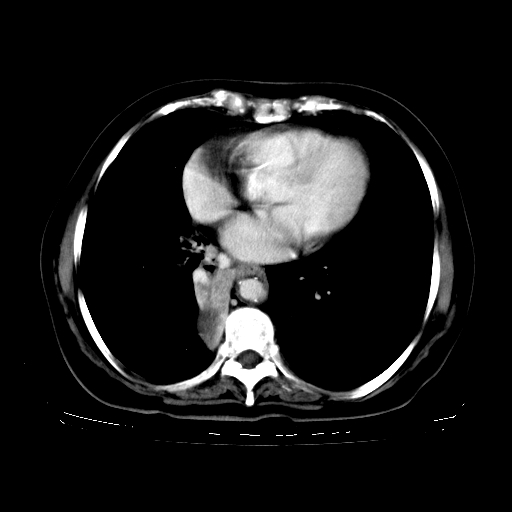

标题: CT23067:女,70岁,咳嗽、咳痰一个月,低热一周。 [打印本页]

女,70岁,咳嗽、咳痰一个月,低热一周。

1.左上肺结核,部分纤维化。右肺中下叶部分肺不张,内见液化、坏死及点状钙化,右中下叶支气管壁增厚、管腔狭窄,见多个点状钙化,结合临床考虑支气管内膜结核,建议痰检查抗酸杆菌并参考血沉。两肺多个小圆点状高密度灶,境界模糊,多考虑结核肺内播散。但本人年龄较大首先应支气管镜检以除外右肺癌。

2.胸主动脉夹层。